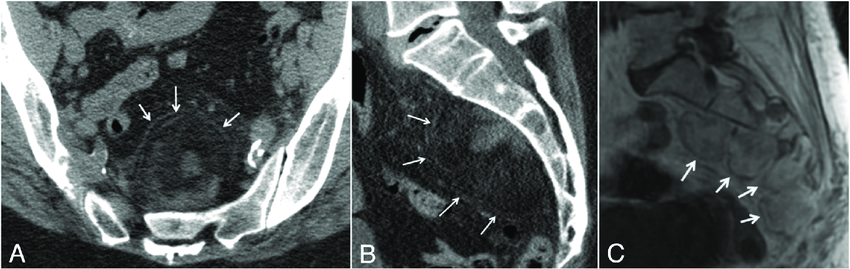

paraganglioma at the organ of zuckerkandl

faints when he pees

post-mictruition syncope = bladder paraganglioma

syncope when pees

MIBG-123 uptake at the bladder wall in a bladder paraganglioma

MIBG does not have renal or bladder uptake, so abnormal activity there = paraganglioma